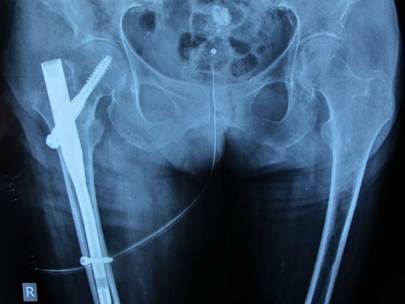

Σχετικά με τα απαρεκτόπιστα κατάγματα του αυχένα του μηριαίου οστού αντιμετωπίζονται κατά κανόνα με κοχλίωση, ενώ τα παρεκτοπισμένα με αρθροπλαστική συνήθως ημιαρθροπλαστική ή ολική αρθροπλαστική ισχίου σε νεότερους και δραστήριους ασθενείς. Τα διατροχαντήρια και υποτροχαντήρια κατάγματα αντιμετωπίζονται με ανοικτή ανάταξη και εσωτερική οστεοσύνθεση, κυρίως με ενδομυελικό ήλο ισχίου ή, σε σταθερές περιπτώσεις, με ολισθαίνοντα κοχλία. Η μη χειρουργική αντιμετώπιση είναι εξαιρετικά περιορισμένη και αφορά μόνο πολύ σταθερά κατάγματα ή ασθενείς με ιδιαίτερα επιβαρυμένο ιατρικό ιστορικό και ελάχιστη προϋπάρχουσα κινητικότητα.